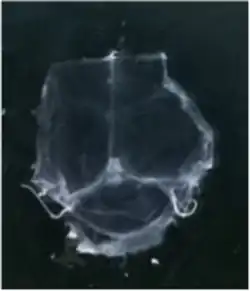

Although several studies proposed the existence of lymphatic vessels in the dura mater, the presence of the meningeal lymphatic system was accepted in 2015, when two independent studies published by Louveau et al.[1] and Aspelund et al.[2] provided convincing data using novel methods. Louveau et al. noticed an unusual alignment of immune cells along the dural sinus using a meningeal whole-mount technique. Using lymphatic endothelial cell-specific markers and electron microscopy, the authors found that the immune cells were not inside blood vessels, but rather were organized inside lymphatic vessels within the meninges, a system of membranes that envelop the brain and spinal cord.[1]

To visualize the dura mater using immunohistochemistry, the dura must first be fixed within the skullcap. It is prepared by cutting around the base of the skull (inferior to the post-tympanic hook) and removing the lower portion of the skull and brain. Following fixation, the dura can be dissected out of the skullcap as a single piece of tissue that can be utilized for histological analysis.[12]

The meningeal lymphatic system is composed of a network of vessels along the dural sinus in the dura which express lymphatic endothelial cell marker proteins, including PROX1, LYVE1, and PDPN. The vessels extend along the length of both the superior sagittal and transverse sinuses and directly connects to the deep cervical lymph nodes.[1] These meningeal lymphatic vessels drain down and exit the skull along the dural venous sinuses and meningeal arteries. Meningeal lymphatic vessels also drain out of the skull alongside cranial nerves and through the cribriform plate. Molecular profiling indicates that the vessels are conventional lymphatic vessels: they express high levels of PROX1, LYVE1, PDPN and VEGFR3, but low levels of PECAM1. Meningeal lymphatic vessels absorb cerebrospinal fluid and drain into the deep cervical lymph nodes.[2]

Several unique attributes differentiate meningeal lymphatic vessels from lymphatic vessels in peripheral organs. Compared to peripheral lymphatic vessels, the meningeal lymphatic network is markedly less complex, with far less tissue coverage and lymphatic branching. Furthermore, meningeal lymphatic vessels are generally smaller than those in the periphery and display a structural homogeneity along the dural sinuses, remaining thinner and mostly unbranched along the superior sagittal sinus while growing larger and more branched along the transverse sinuses.[1] The meningeal lymphatic vessels are also unique for their scarcity of valves, which prevent back-flow of lymph. While the vessels in the superior parts of the skull were mostly devoid of valves, the larger lymphatic vessels of the basal parts only contain scattered valves.[2]